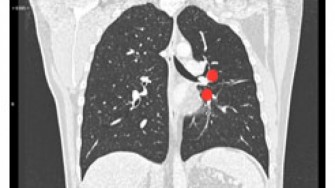

Les tumeurs carcinoïdes expriment le VEGF. Des études chez l’animal utilisant des anticorps anti-VEGF ont montré une activité anti-tumorale. 44 patients présentant une tumeur carcinoïde avancée (essentiellement métastatique) reçoivent soit du bévacizumab en monothérapie (23) soit de l’interféron pégylé (21) pendant 18 semaines, puis une combinaison des 2 soit à la progression, soit après les 18 semaines. Dans le bras bévacizumab seul, on obtient : 18% de réponse partielle et 77% de maladie stable ; dans le bras interféron seul : une absence de réponse même partielle et 68% de maladie stable. La PFS dans le bras bévacizumab seul est de 95% à 18 semaines vs 68% dans le bras interféron. La PFS médiane est de 63 semaines pour tous les patients. Les auteurs concluent que le bévacizumab a un réel potentiel dans la prise en charge des tumeurs carcinoïdes avancées avec un impact en réponse et en DFS. Cependant il s’agit d’une phase II. Les résultats de l’essai randomisé de phase III du SWOG S0518 comparant octréoïde + bévacizumab et octréoïde + interféron apportera plus de renseignements sur la place du bévacizumab. A suivre !